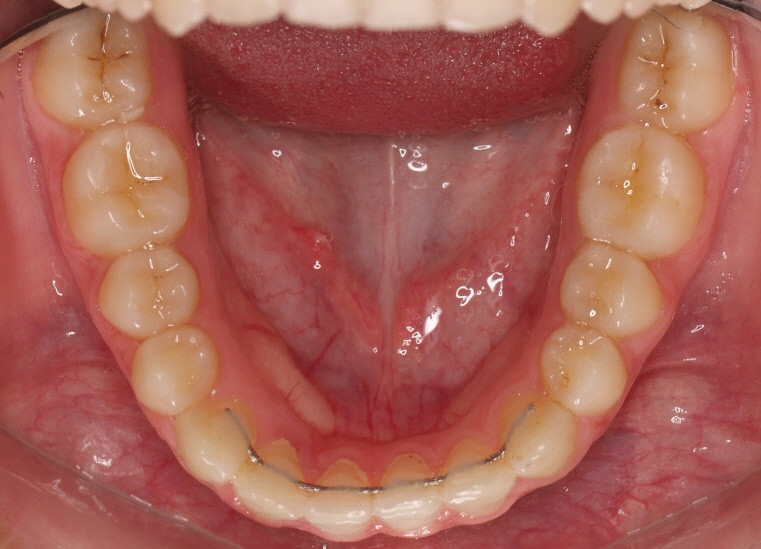

Clase II paciente 15 años

Con lo que decide realizarse un tratamiento de ortodoncia de duración de 24 meses con brackets damon Q.

CASO COMPLETO: